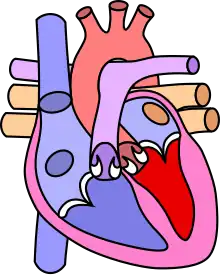

Dans le cœur normal, la cloison qui sépare les ventricules droit et gauche, dénommée « septum interventriculaire », est totalement hermétique. Une CIV correspond à la présence d'un orifice plus ou moins large dans cette cloison, permettant le passage direct du sang d'un ventricule à l'autre. Les conséquences de cette malformation dépendent essentiellement de la taille de la communication. Dans la plupart des cas, l'orifice est petit : ces CIV sans conséquence réellement gênante sont appelées « maladie de Roger ». L'évolution d'une CIV dépend de sa localisation sur le septum, certaines étant susceptibles de se fermer spontanément dans les mois ou années suivant la naissance.

Différentes localisations des CIV

La complexité de la formation embryologique de la cloison interventriculaire, nécessitant l'alignement et la fusion de quatre constituants explique, au moins en partie, la fréquence des CIV.

Connaître non seulement la taille mais aussi la localisation d'une CIV a un double intérêt :

- C'est le cas des CIV qui siègent dans le septum d'admission (partie 1 en rouge sur le schéma), fréquemment associée à une Trisomie 21, et de celles qui siègent dans le septum sous-aortique (partie 4 en bleu sur le schéma), parfois associées à une anomalie du chromosome 22 (Microdélétion 22q11) ;

- dans certaines localisations, la CIV est susceptible de diminuer de taille, voire de se fermer totalement de façon spontanée alors que dans d'autres, ce mécanisme de guérison spontané n'est jamais observé.

- les CIV siégeant dans le septum membraneux (partie 3 en jaune sur le schéma) et encore plus les CIV musculaires situées dans la partie 2 (en vert sur le schéma) sont fréquemment capables de « se guérir toutes seules » (à condition que l'état de l'enfant permette d'attendre).

- les CIV situées dans les parties 1 (septum d'admission) et 4 (septum sous-aortique) ne se ferment jamais spontanément et devront donc, sauf exception, être opérées tôt ou tard.